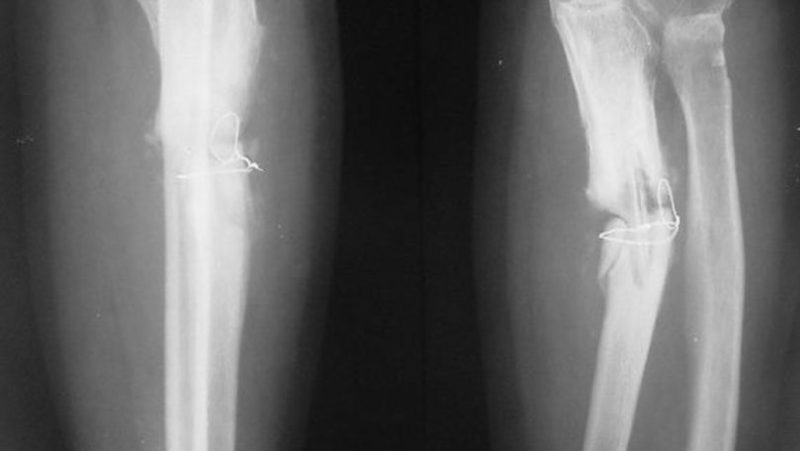

Testele clinice au arătat rezultate promițătoare, inclusiv în cazuri unde fracturile ar fi fost dificil de tratat prin metode clasice. Tehnologia are un potențial ridicat pentru utilizare în spitale, în situații de urgență sau în intervenții minim invazive.